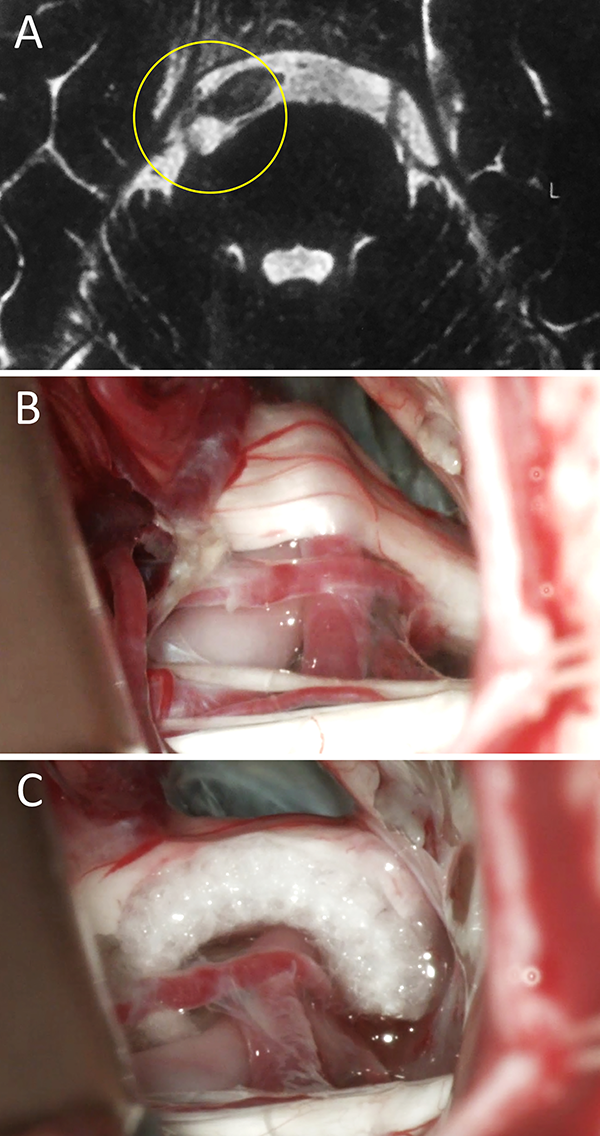

Figura 2:

Varón de 45 años de edad con clínica de NT típica refractaria al tratamiento farmacológico. En RM no se evidencio CNV alguno, por esto su neurólogo de cabecera indicó tratamiento farmacológico durante más de un año. Finalmente consultó con nuestro equipo y se decidió conducta quirúrgica en virtud a la clínica. En el intraoperatorio se evidenció un claro CNV del lado izquierdo. Evolucionó favorablemente con remisión del cuadro doloroso. A) RM preoperatoria; B) hallazgo intraoperatorio, CNV ; C) colocación de teflón. NT: neuralgia trigeminal; RM: resonancia magnética; CNV: conflicto neurovascular.